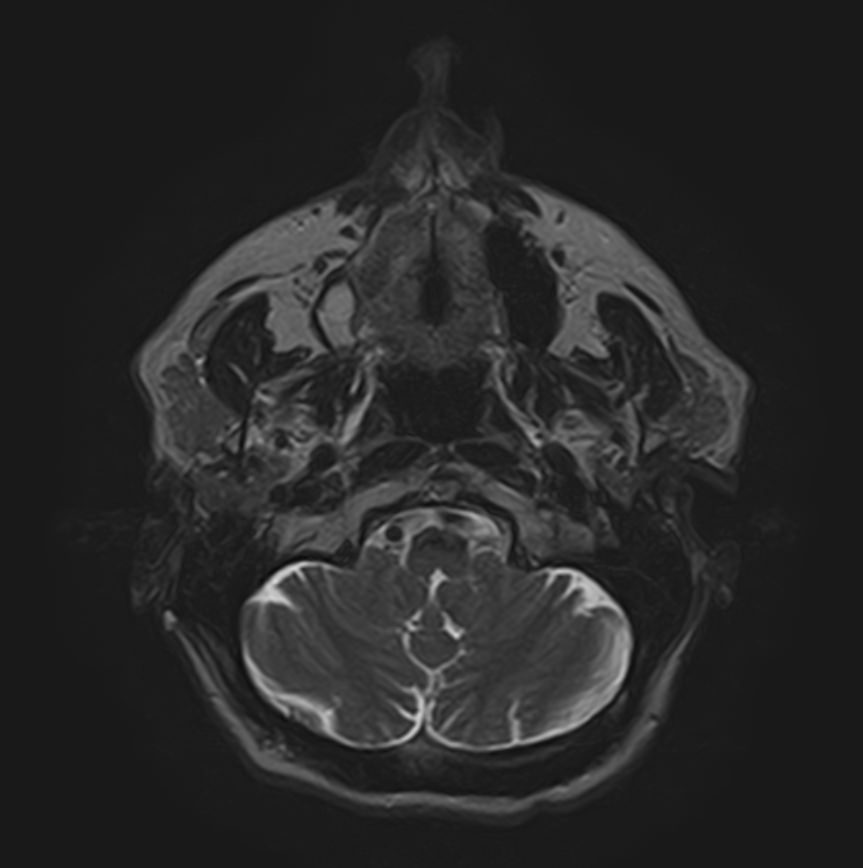

Магнитно-резонансная томография (МРТ) мягких тканей лица – это неинвазивное диагностическое исследование, которое использует магнитное поле и радиоволны для получения детализированных изображений структур мягких тканей в области лица. МРТ мягких тканей лица позволяет визуализировать мышцы, жир, нервы, сосуды и другие мягкотканные структуры, что помогает в диагностике различных заболеваний и патологий, таких как: